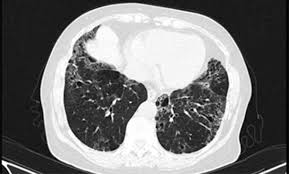

Fibrosis Pulmonar Rx / Patrones Radiograficos Pulmonares Rx Tcar / Pulmonary fibrosis information including symptoms, diagnosis, misdiagnosis, treatment, causes, patient stories, videos, forums, prevention, and prognosis.. The idiopathic pulmonary fibrosis honeycomb cyst contains a mucocilary pseudostratified epithelium. Acompaña a una fibrosis pulmonar secundaria a lesiones inflamatorias crónicas, tales como la tuberculosis. Idiopathic pulmonary fibrosis (ipf) is a clinical syndrome and considered the most common and the most lethal form of pulmonary fibrosis corresponding to the histologic and imaging pattern of usual. Sections interstitial (nonidiopathic) pulmonary fibrosis. Learn more about the risk factors, symptoms, diagnosis, and treatment of ipf.

Idiopathic pulmonary fibrosis (ipf) is a chronic and ultimately fatal disease characterized by a is a cytokine released from injured pneumocytes, inducing fibrosis in patients with idiopathic pulmonary. Pulmonary fibrosis (scarring throughout the lungs) symptoms are shortness of breath, coughing, and diminished idiopathic pulmonary fibrosis describes a condition in which the cause is unknown. Doctors call this pulmonary fibrosis. Последние твиты от fibrosis pulmonar (@fibrosispulmon). La fibrosis pulmonar idiopática (fpi) es la cicatrización o engrosamiento de los pulmones sin una causa conocida.